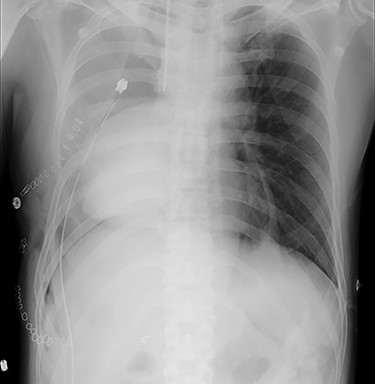

He was transferred to the postoperative care unit and no significant symptoms and hemodynamic impairment were observed at that time. He complained of feeling unwell 18 h postoperatively and developed hypotension (89/57 mmHg with noradrenaline 0.015 μg/kg/min). Routine chest radiography revealed unexpected cardiac herniation into the right-sided thoracic cavity (Fig. 1). The patient was immediately transferred to the operating room and underwent emergency thoracotomy. Cardiac herniation had occurred secondary to tearing of sutures on the posterior aspect of the ePTFE sheet. We placed the heart back within the pericardium and repaired the tears by fixing another ePTFE sheet to close the defect between the posterior pericardium and the previously placed ePTFE sheet using horizontal mattress and continuous sutures (Fig. 2). The postoperative course was uneventful, and he was discharged 43 days after second operation. He died of tumor progression 2 years after the second operation. However, Cardiac herniation did not recur postoperatively.

Chest radiography showing cardiac herniation into the right-sided thoracic cavity.